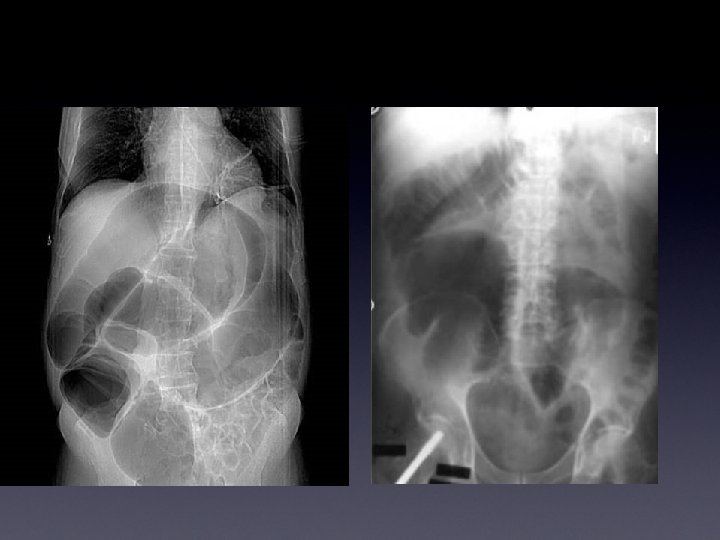

FALSO ADDOME ACUTO • Rx Diretta Addome: notevole distensione del colon, in particolare dellaregione cecale (attorno ai 10 cm) • Tac Addome: conferma del quadro radiologico

FALSO ADDOME ACUTO MALATTIA CEREBROVASCOLARE STIPSI OSTINATA CON ANSE INTESTINALI ABNORMEMENTE DISTESE DILATAZIONE DEL CECO ALL’RX DIRETTA ADDOME E ALLA TAC DI CIRCA 10 cm

DIAGNOSI SINDROME DI OLGIVIE ACPO Mortalità 15 -50%

FALSO ADDOME ACUTO Sindrome dovuta ad uno squilibrio dell’attività motoria del colon da parte del sistema neuro-vegetativo viscerale che determina Una pseudo ostruzione acuta del grosso intestino con notevole dilatazione della regione cecale